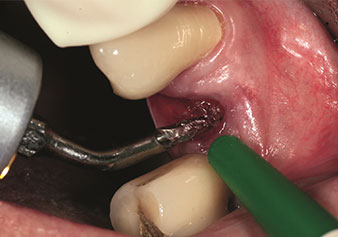

Internal sinus lift

W&H also offers the perfect solution for the internal sinus lift.

Following preparation of the maxillary sinuses with the corresponding instrument set (Fig. 3), the new Z35P instrument (Fig. 4) is used to lift the membrane hydrodynamically. The same instrument set can also be used for piezosurgical preparation of the implant bed in increasing diameters (Figures 3 and 4 included with the kind permission of Dr Mario Kirste, Frankfurt/Oder).

Preparation of implant bed with I4P instrument

Fig. 3: Preparation of implant bed with I4P instrument. Photo: © Dr Mario Kirste (Frankfurt / Oder)